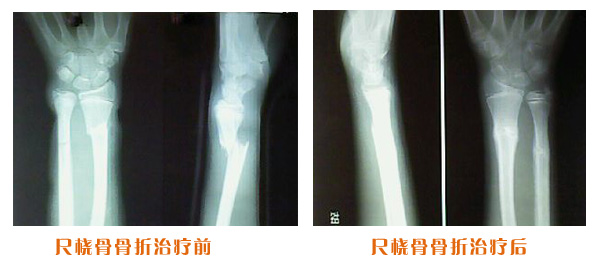

肥城市安駕莊梁氏骨科醫(yī)院是一所以梁氏手法正骨配合膏藥為特色的現代化??漆t(yī)院。

梁氏骨科術始創(chuàng)于清雍正年間,歷經八代,至今已有三百年歷史。據1929年泰安縣志載“梁瑞圖先生,字增生,號蓮峰,安駕莊人,精岐黃并發(fā)明接骨,凡跌打車凡跌打車軋皮不破而碎骨者......【詳細】 |